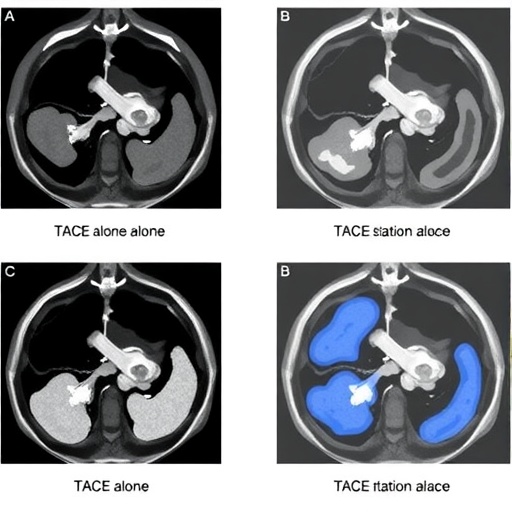

The authors of the correction examined the outcomes associated with TACE alone against those experiences alongside synchronous ablation. This study is pivotal as it navigates through unchartered waters of comparative effectiveness research within a field that has historically leaned towards singular treatment approaches. The correction sheds light on previously published findings, underscoring methodological inconsistencies, which is paramount for advancing clinical understanding.

Central to their findings is the potential for enhanced therapeutic efficacy when combining TACE with synchronous ablation. Using an integrated approach not only targets the tumors more aggressively but also reduces the likelihood of recurrence, which is a common concern among patients. The synergy of these techniques may play a vital role in optimizing patient prognoses, thereby setting new treatment standards in the realm of neuroendocrine neoplasms with liver metastases.

The study presents a careful examination of patient outcomes, revealing not only a statistically significant decrease in tumor size but also an improvement in survival rates when the combined approach was utilized. Strategies that incorporate both TACE and synchronous ablation could eventually become the gold standard, shifting clinical practice paradigms. The exploration of such methods aligns with a broader trend in oncology towards personalized, multi-modal treatment strategies.

Within the context of treatment modalities, the role of imaging in facilitating the precise delivery of therapy is paramount. The correction emphasizes the importance of advanced imaging techniques in identifying and tracking liver metastases effectively. As technology continues to evolve, the capabilities of imaging can enhance the accuracy of both TACE and ablation procedures, promoting more effective interventions and better outcomes.